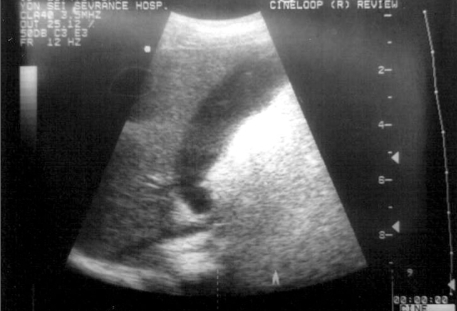

Abdominal Ultrasound Identified Two Foci Of Hepatolithiasis In Segment Download Scientific Diagram